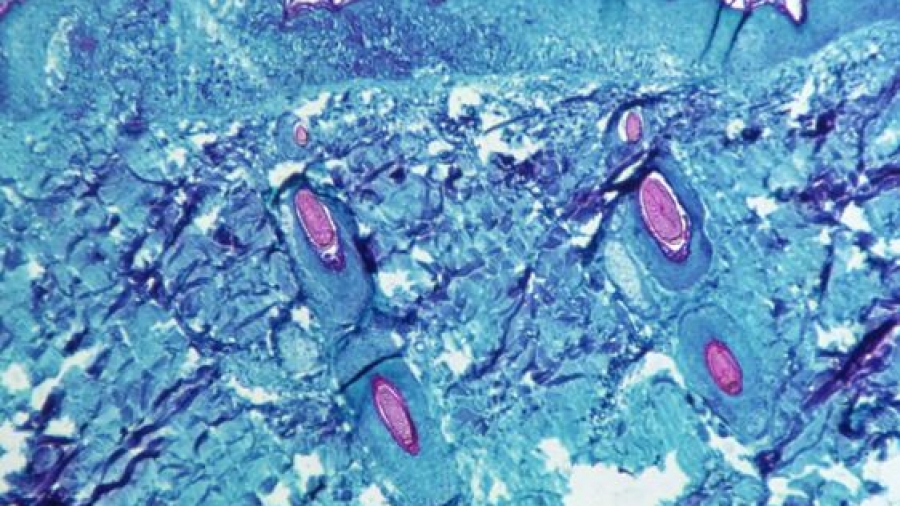

Η ευλογιά των πιθήκων, μολυσματική ασθένεια συνήθως με ήπια συμπτώματα, είναι ενδημική σε τμήματα της δυτικής και της κεντρικής Αφρικής, ενώ εξαπλώνεται μέσω της στενής επαφής, κάτι που σημαίνει πως μπορεί να περιοριστεί σχετικά εύκολα, με απομόνωση και τήρηση των κανόνων υγιεινής.

Η ευλογιά των πιθήκων είναι μια σπάνια, λοιμώδης ασθένεια, παρόμοια με την ανθρώπινη ευλογιά που εξαλείφθηκε το 1980.

Μολονότι είναι πιο ήπια και οι περισσότεροι ασθενείς αναρρώνουν μέσα σε μερικές εβδομάδες, σε σπάνιες περιπτώσεις μπορεί να αποδειχθεί μοιραία.

Τα συμπτώματά της περιλαμβάνουν πυρετό, πονοκέφαλο, μυικούς πόνους, πρήξιμο στους λεμφαδένες, ρίγη και κόπωση.

Επίσης οι ασθενείς μπορεί να εμφανίσουν δερματικά εξανθήματα, τα οποία συχνά ξεκινούν από το πρόσωπο και εξαπλώνονται σε άλλα σημεία του σώματος, περιλαμβανομένων των γεννητικών οργάνων.

Δεν υπάρχει θεραπεία για την ευλογιά των πιθήκων, η οποία μεταδίδεται από την επαφή με τον μολυσμένο ασθενή ή με τα σωματικά υγρά του, περιλαμβανομένου του σάλιου.

Ο ιός, ο οποίος προκαλεί πυρετό, μυϊκούς πόνους, πρησμένους λεμφαδένες, ρίγη, εξάντληση και εξανθήματα που μοιάζουν με της ανεμοβλογιάς (φλύκταινες) στα χέρια και το πρόσωπο, σπάνια είναι θανατηφόρος και συνήθως υποχωρεί μετά από δύο έως τέσσερις εβδομάδες, σύμφωνα με τον ΠΟΥ.